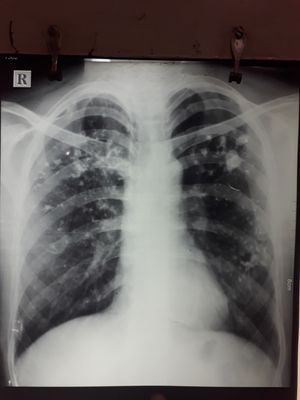

Past h/o ATT for 9 month. C/o haemoptysis since week and DOE ch smoker

TB? Pulmonary fibrosis? Alveolar hemorrhage? I dont know. đŸ˜Ģ

Metastasis lung cancer -Multiple nodules see in the both lungs

Metastasises in both lungs